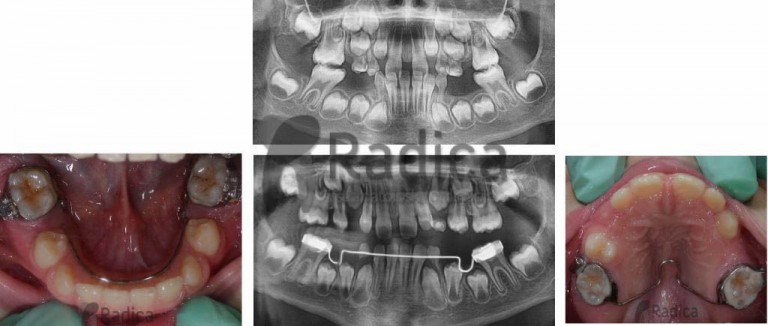

U slučaju da ipak dođe do preranog gubitka mliječnih zuba preporučuje se napraviti držače mjesta, transplatinalni i/ili lingvalni lukovi koji sprječavaju pomak „šestica“ i čuvaju mjesto za trajne nasljednike.

Nažalost, najveći broj ortodontskih pacijenata u Hrvatskoj upravo su oni koji su prerano izgubili mliječne i/ili trajne zube jer ih nisu prali niti odlazili stomatologu.

Ortodontske anomalije uzrokovane preranim gubitkom mliječnih zuba i poslije gubitkom trajnih u suvremenom su svijetu rijetka pojava, a kod nas je gotovo svako treće dijete bez trajnih “šestica”.